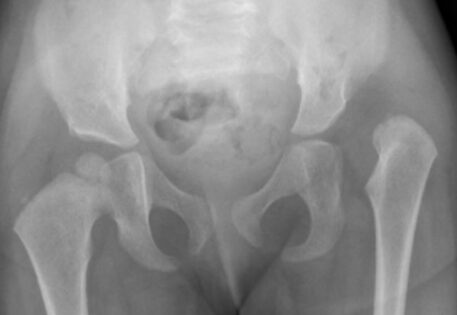

Hip dysplasia can manifest in various syndromes, including Prader-Willi syndrome, arthrogryposis, caudal regression syndrome, and Kabuki syndrome. Syndromic hip dysplasia cases in Dubai often involve more pronounced anatomical distortions, posing greater challenges in treatment and higher recurrence risks. Dr. Qureshi, a child orthopaedic doctor in Dubai, is experienced in addressing these complex cases, providing specialised care and management for each unique condition.

Dr. Qureshi has successfully managed numerous cases of syndromic hip dysplasia, employing investigations such as arthrography and CT imaging to assess reconstruction feasibility and plan surgical interventions. The treatment strategy is customarily crafted as a tailored combination of different techniques to address distinct components and contributory factors contributing to the dislocation.